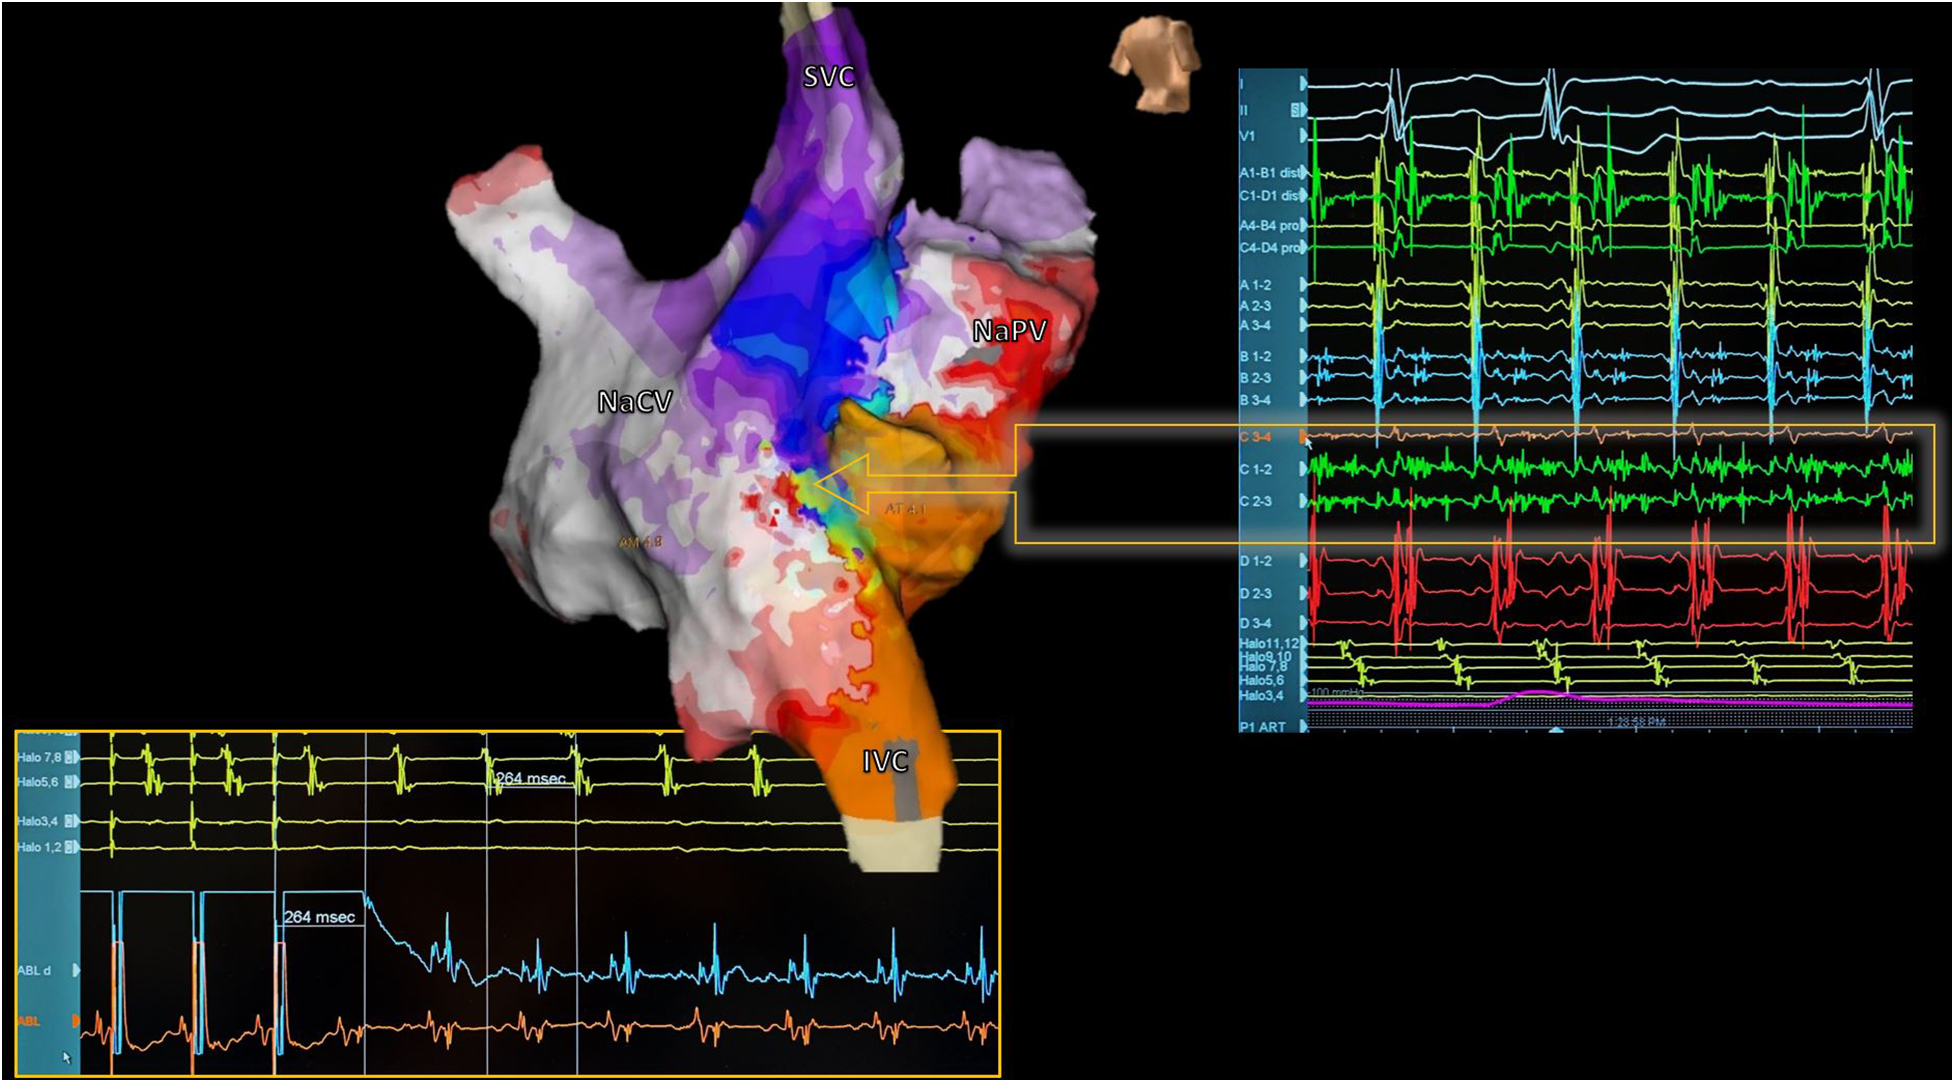

Figure 6

Reentrant atrial tachycardia electroanatomical mapping. Electroanatomic activation map of both neoatria during atrial tachycardia in a patient with corrected d-TGA using the Senning technique (Posterior view). Septal activation shows reentry-compatible activation (Arrow): Careful analysis of electrograms during mapping with a multipolar catheter identified a zone with fragmented and pandiastolic electrograms highly suggestive of the protected isthmus of the tachycardia (Right). At the bottom of the image, the catheter ablation maneuver positioned in this zone is shown, confirming the diagnosis. The tachycardia resolved during the first radiofrequency application. SVC, superior vena cava; IVC, inferior vena cava; NaVC, neocaval atrium; NaPV, neopulmonary vein atrium.